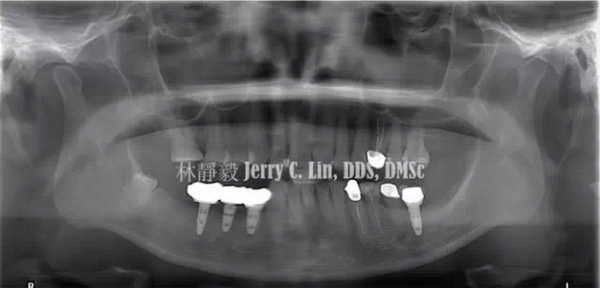

嚴(yán)重種植體周圍炎的處理(二)——林靜毅醫(yī)師